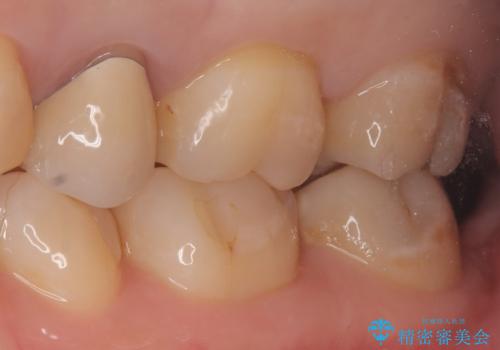

- 定期検診にて虫歯が見つかった患者様です。

金属のインレーの下と、歯と歯の間も虫歯だったため、つなげた形でセラミックインレーにて修復を行なっています。

e-max プレスインレーを用いることで、適合の良い治療ができます。